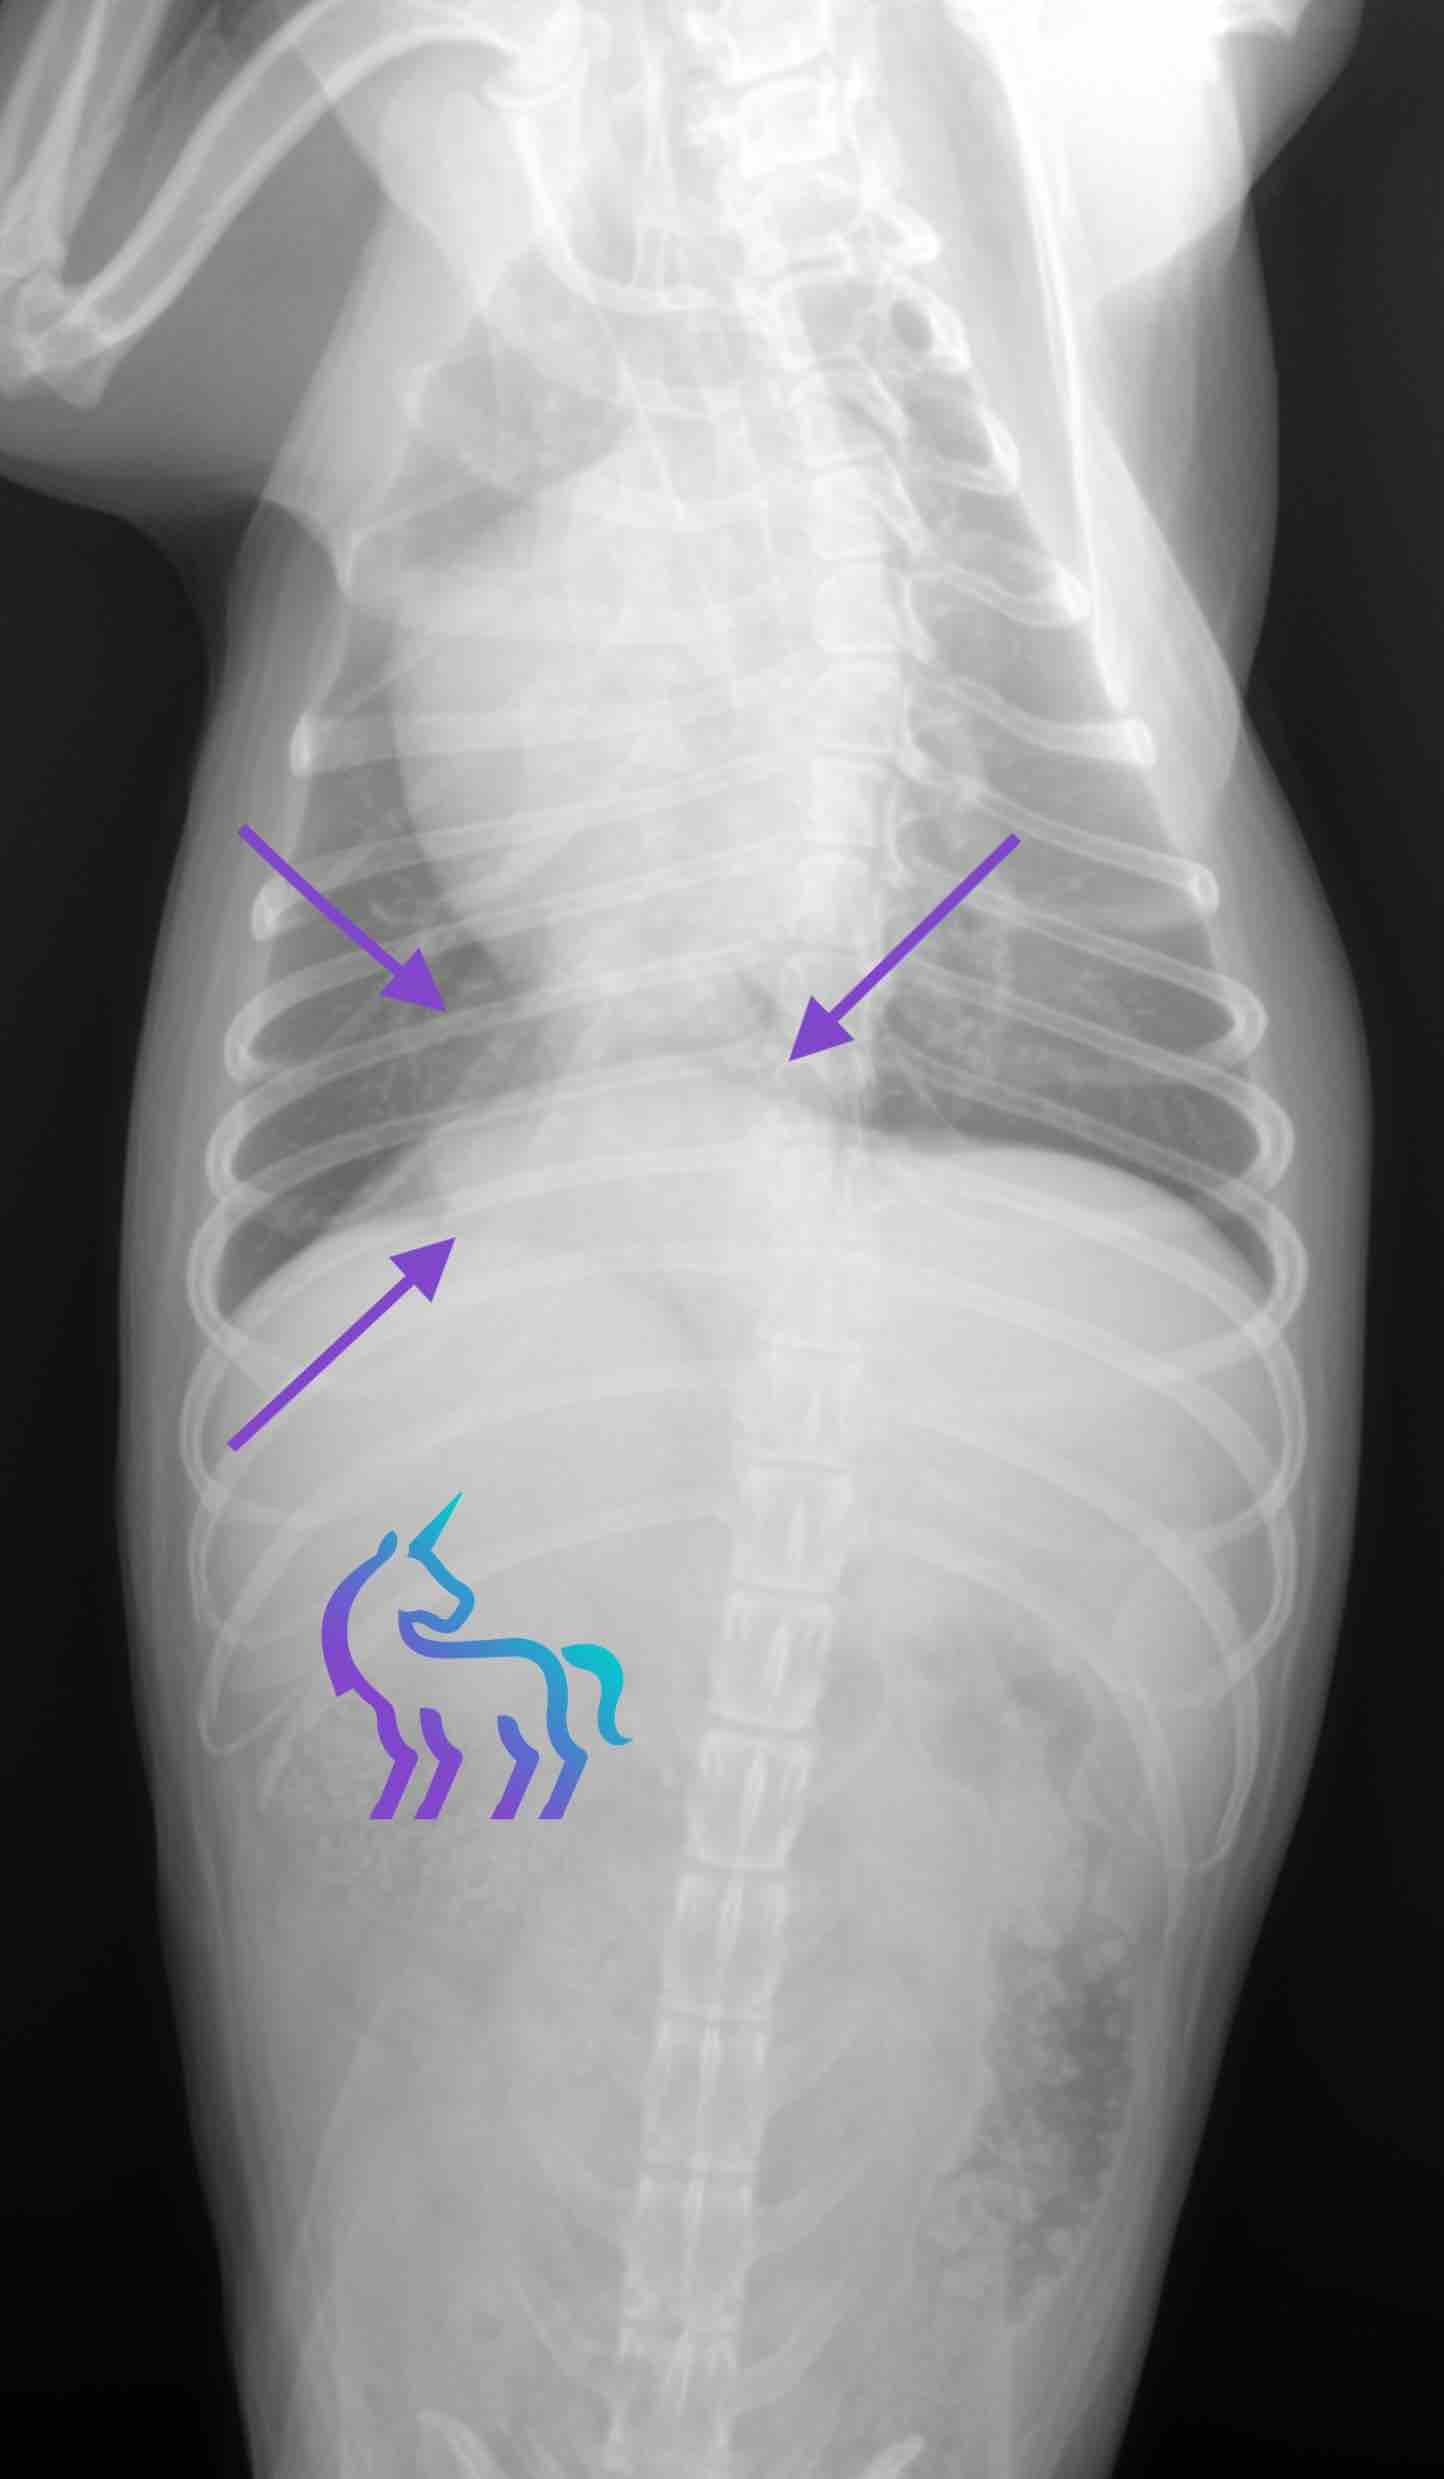

Identification d’une masse pulmonaire du lobe caudal droit

Espèce : ChienRadiographies thoraciques montrant une masse pulmonaire unique, bien délimitée, d’environ 5 cm, située dans le lobe pulmonaire caudal droit.

L’aspect radiographique est compatible avec un carcinome pulmonaire.

Diagnostic : La radiographie permet ici de poser un diagnostic tumoral pulmonaire et d’orienter la prise en charge.